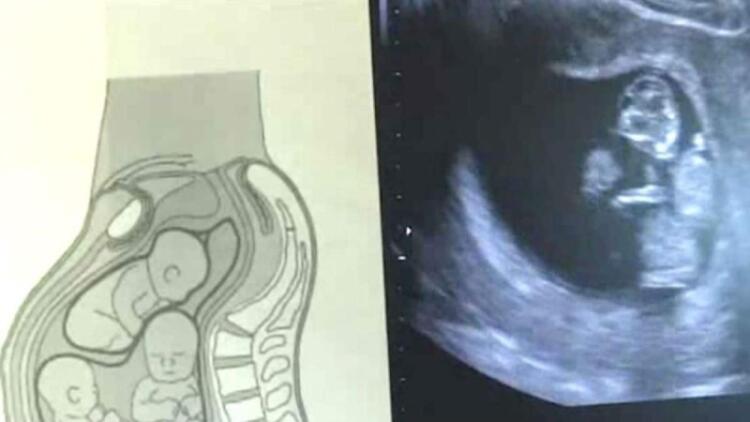

Όταν η Άμπερ επισκέφθηκε τον γιατρό για τον προγραμματισμένο υπέρηχο, ανακάλυψαν όμως και κάτι ακόμα: η εγκυμοσύνη της ήταν μονοχοριονική διαμνιακή (Monochorionic Diamniotic), δηλαδή το ένα έμβρυο είχε χωριστεί στα δύο! Τα δύο από τα μωρά της μοιράζονταν τον ίδιο αμνιακό σάκο, πράγμα πρωτοφανές για τους γιατρούς!